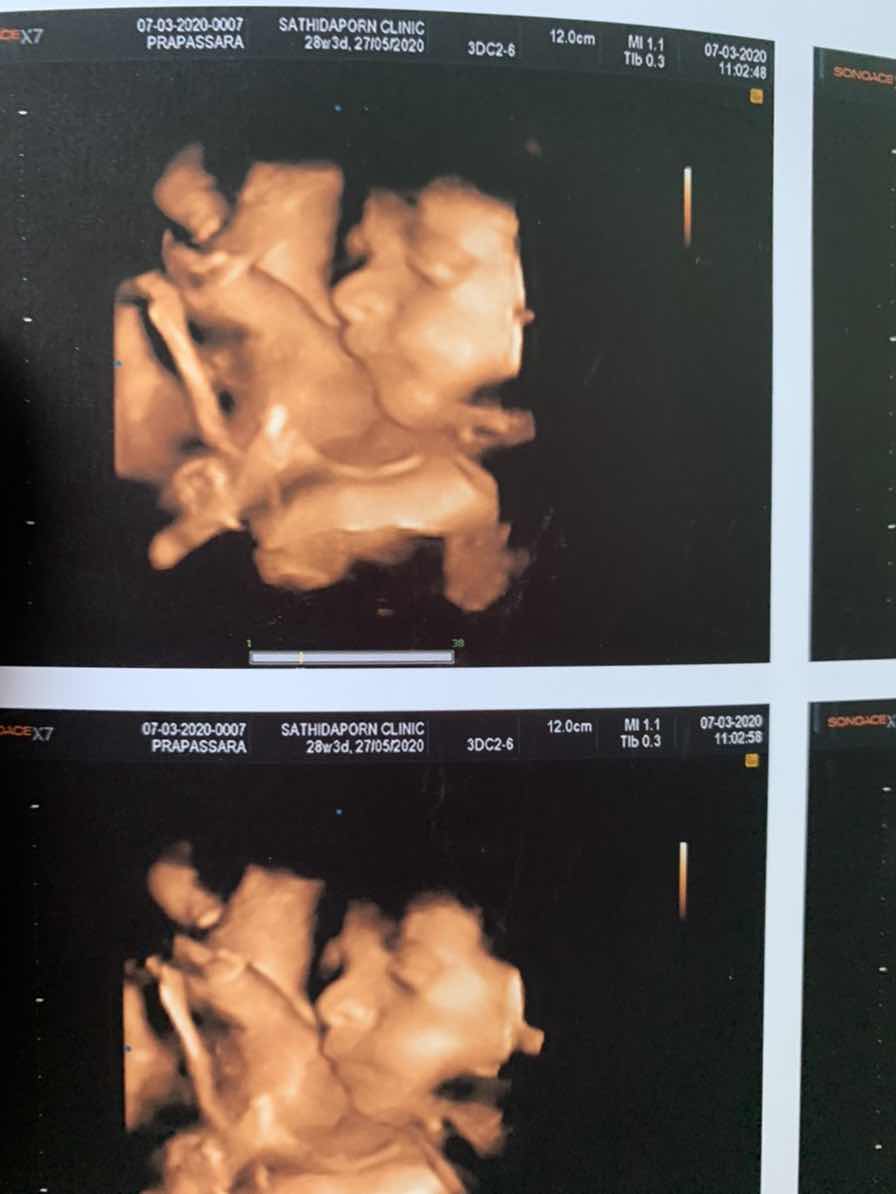

28 week ค่ะ